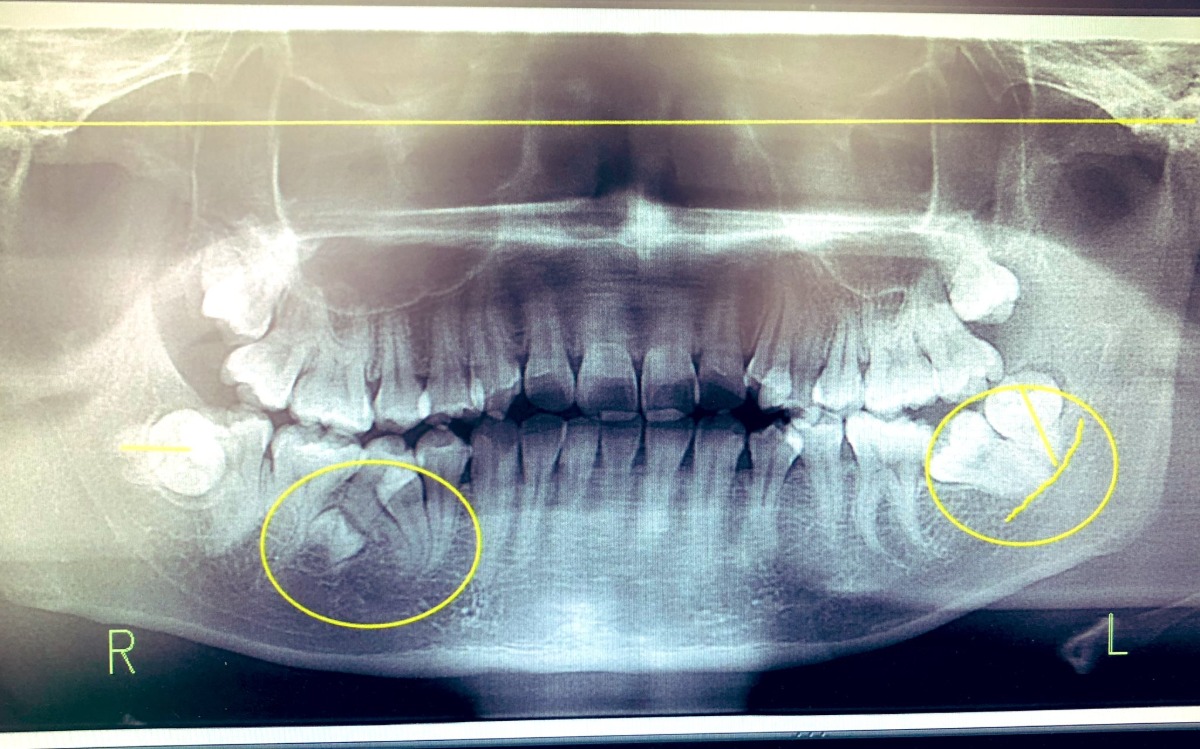

치아가 6개 과잉이라 뽑았더니 추가로 2개 더 난 사람